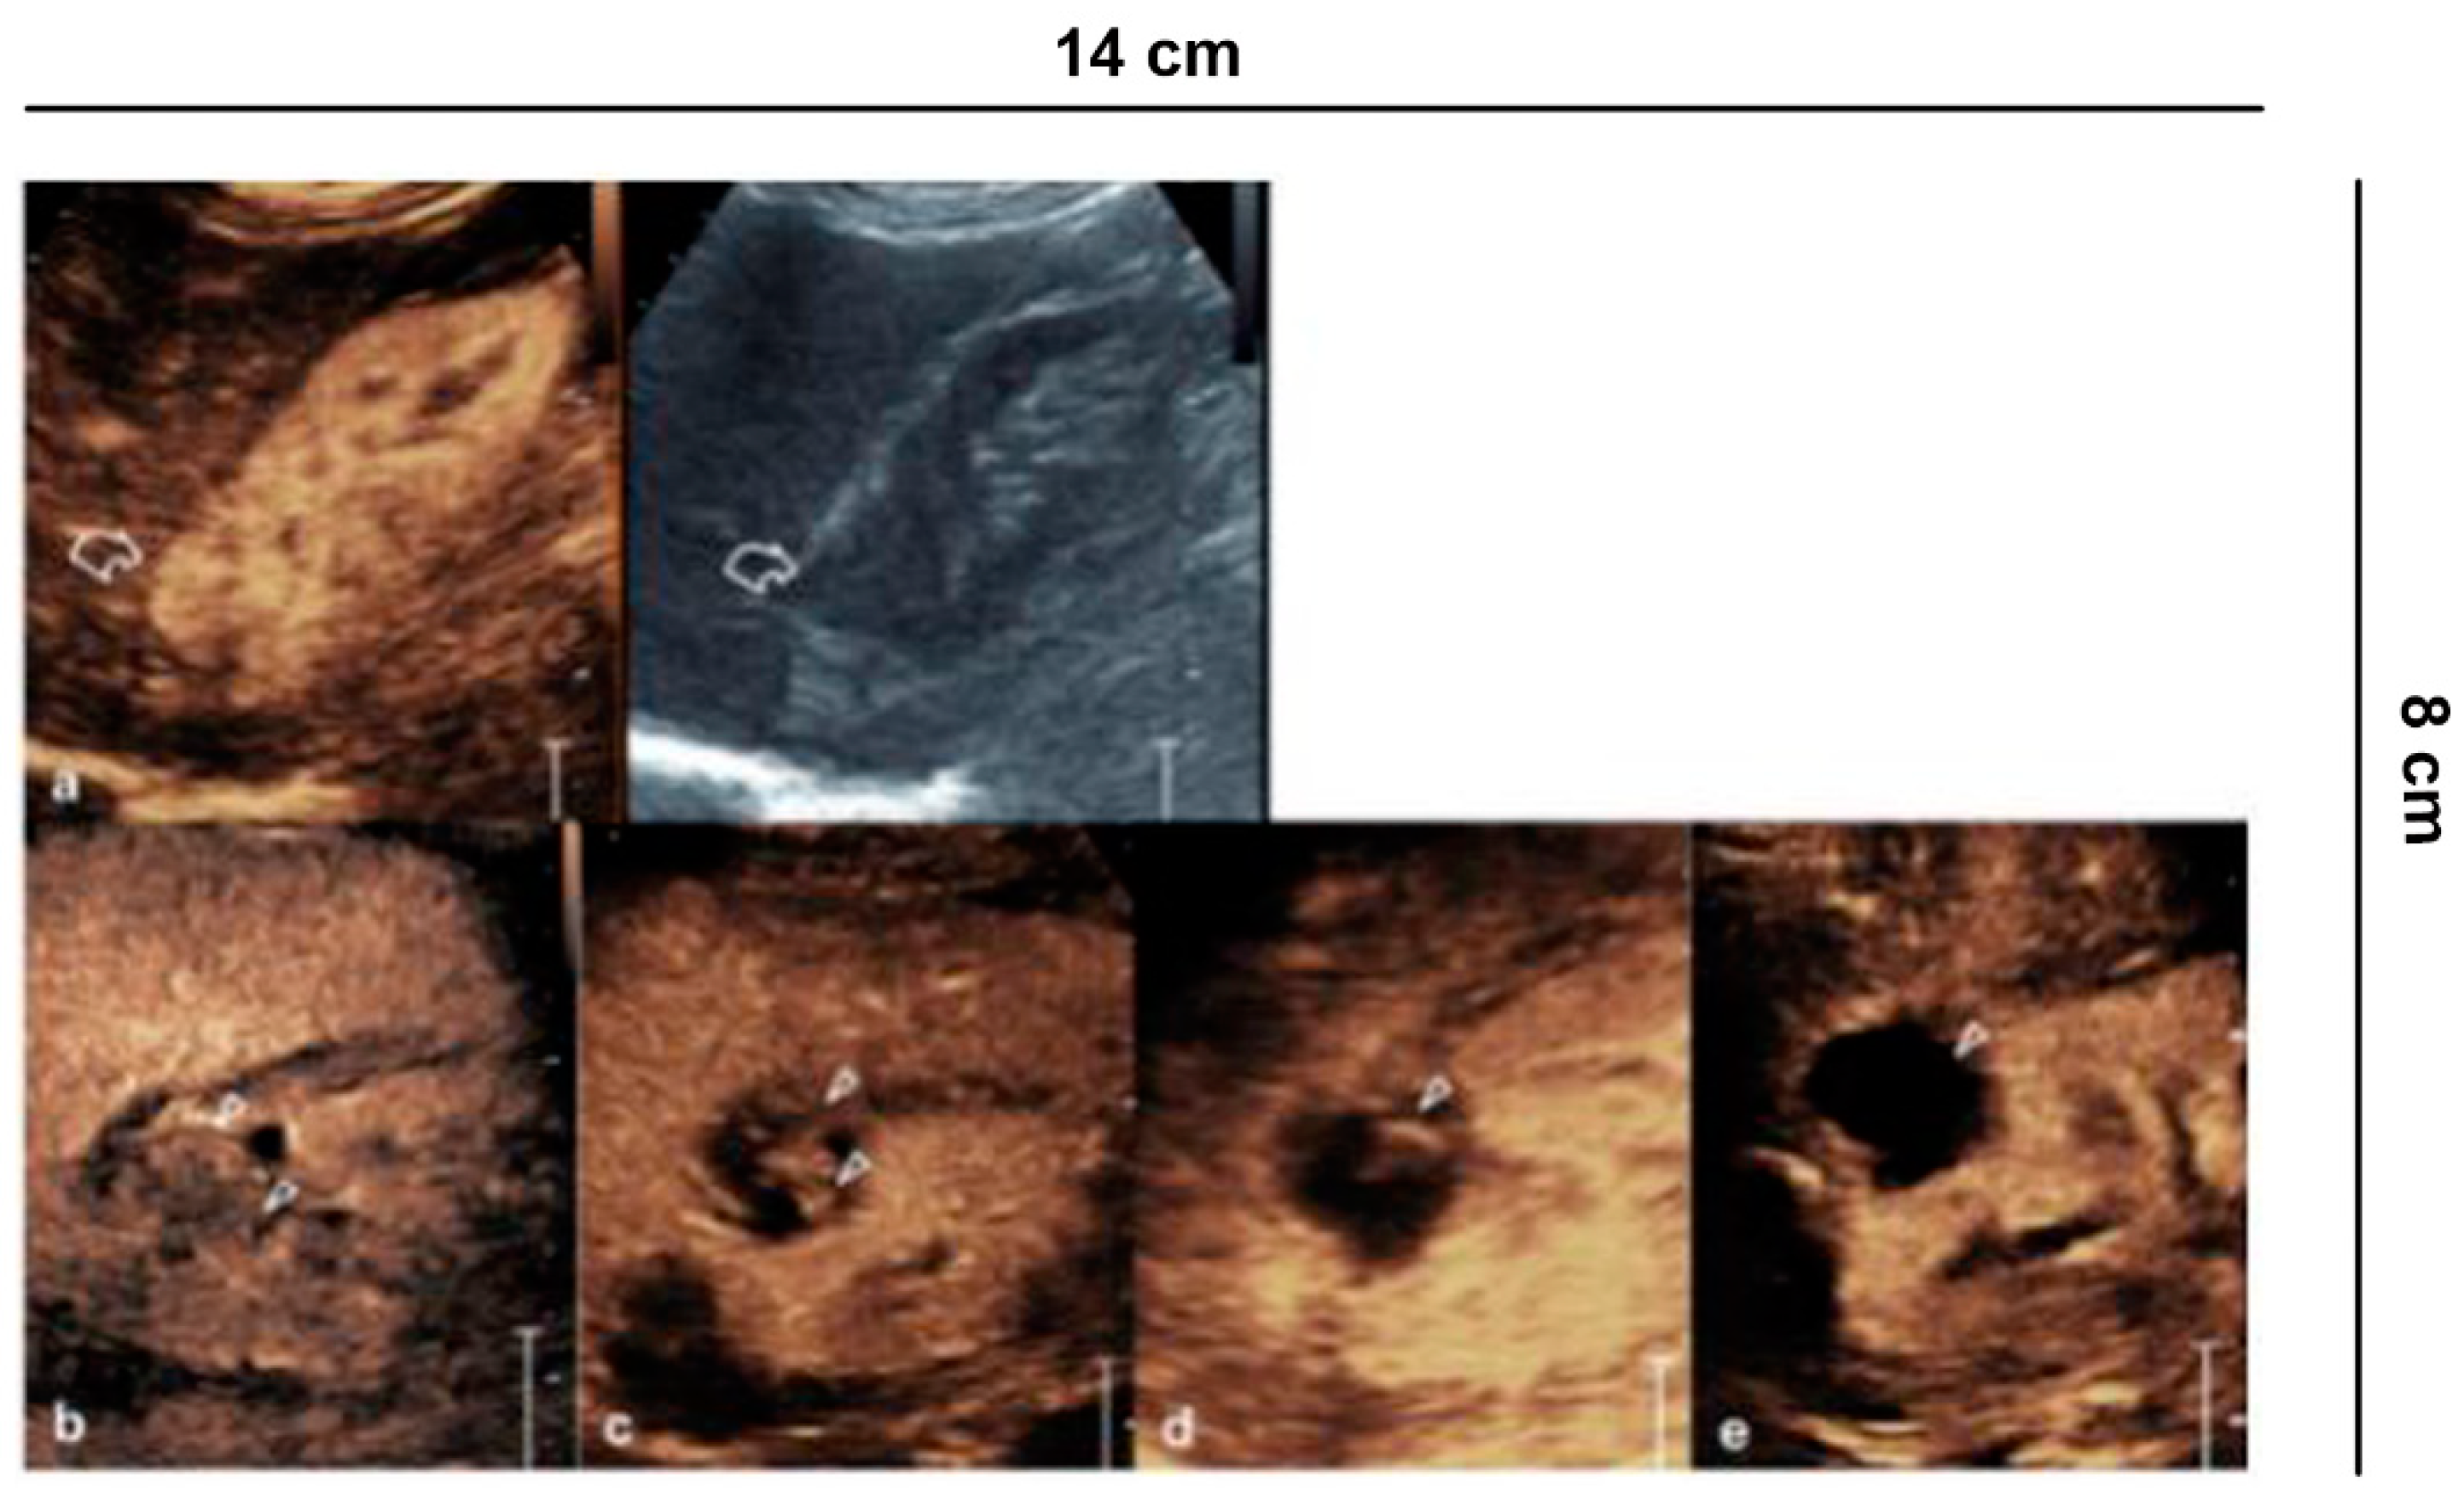

Figure 6.

Ablative technique follow-up. (a) Before the cryo-ablative treatment, CEUS shows an iso-vascular, partially exophytic lesion at the upper pole of the right kidney (curved arrow). After treatment, CEUS shows diffuse and persistent intralesional vascularization (arrowheads) to 24 h (b); at 7 (c) and 14 days (d) there is a progressive reduction of vascularity; after one month (e) the lesion appears completely avascular, a sign of a successful treatment.